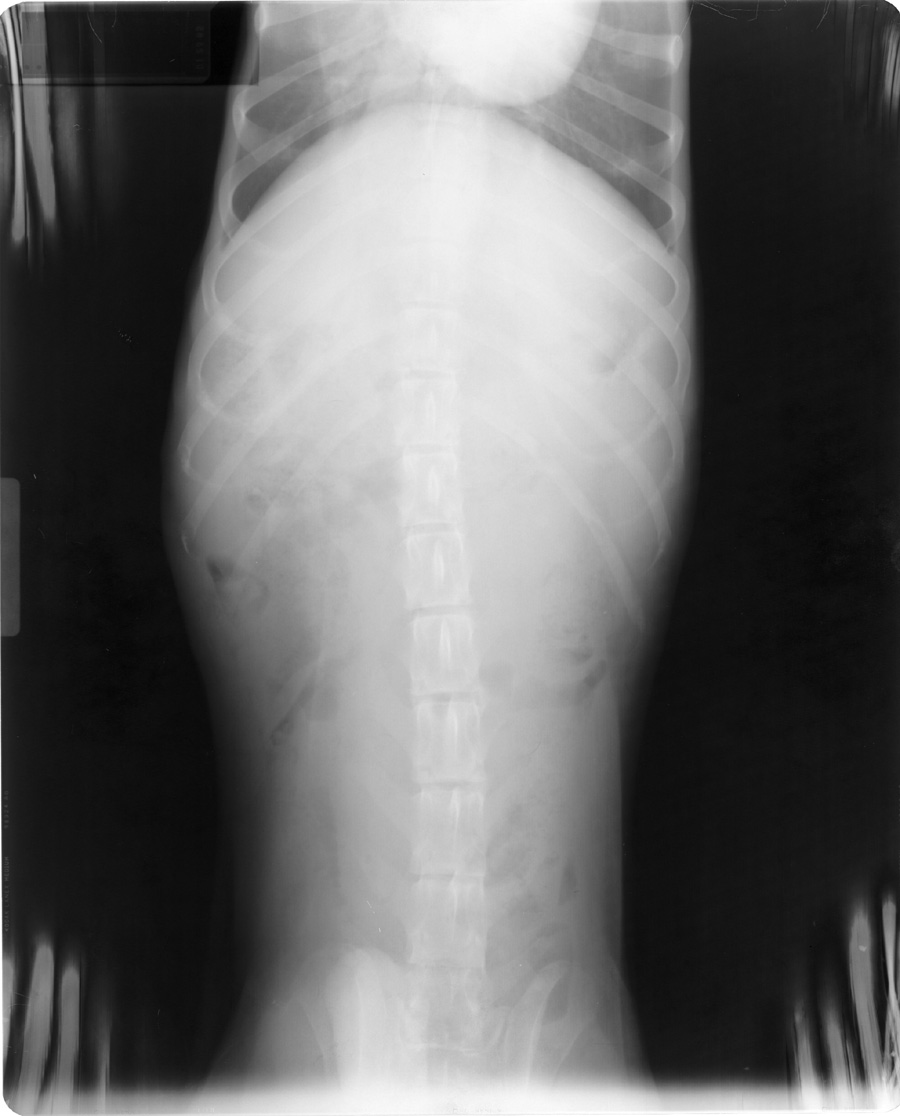

Stuck in Processor

See grid lines.